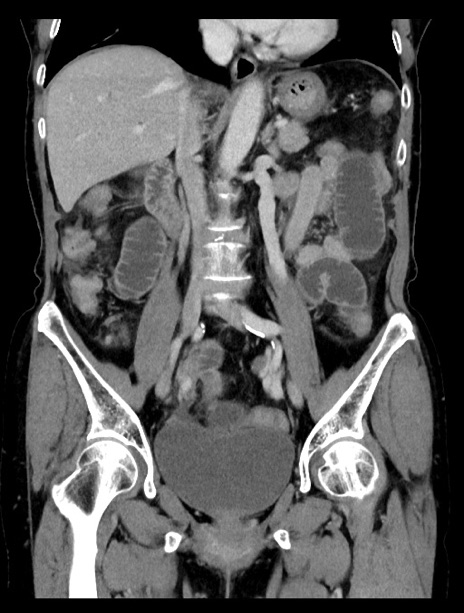

症例23(冠状断像)

【症例】70歳代女性

【主訴】下腹部痛・嘔吐

【現病歴】2日前より腹痛あり。昨日嘔吐あり。症状改善しないため来院。

【既往歴】胃GISTに対して胃部分切除後。

【身体所見】BT 37.1℃、BP 128/77mmHg、腹部:平坦・軟、下腹部に圧痛あり。

【データ】WBC 10200、CRP 0.31

横断像